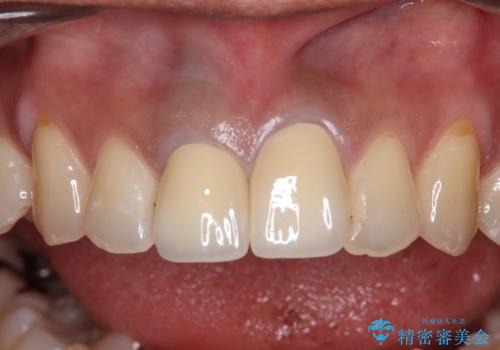

オールセラミッククラウンは金属を使用していないため、本物の歯のような綺麗な仕上がりとなりました。